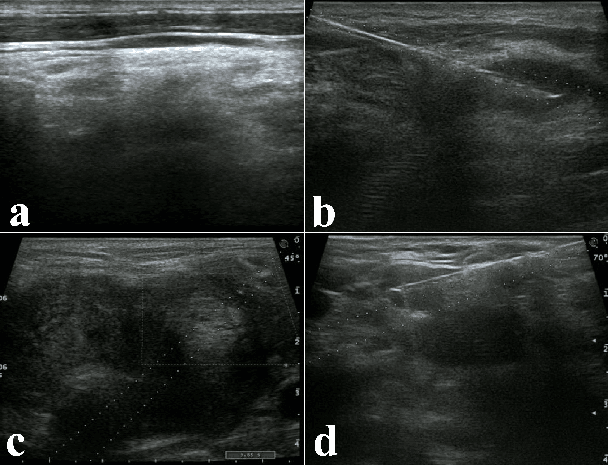

Ultrasound imaging serves as a pivotal tool for diagnosing cervical lymph node lesions. However, the diagnoses of these images largely hinge on the expertise of medical practitioners, rendering the process susceptible to misdiagnoses. Although rapidly developing deep learning has substantially improved the diagnoses of diverse ultrasound images, there remains a conspicuous research gap concerning cervical lymph nodes. The objective of our work is to accurately diagnose cervical lymph node lesions by leveraging a deep learning model. To this end, we first collected 3392 images containing normal lymph nodes, benign lymph node lesions, malignant primary lymph node lesions, and malignant metastatic lymph node lesions. Given that ultrasound images are generated by the reflection and scattering of sound waves across varied bodily tissues, we proposed the Conv-FFT Block. It integrates convolutional operations with the fast Fourier transform to more astutely model the images. Building upon this foundation, we designed a novel architecture, named US-SFNet. This architecture not only discerns variances in ultrasound images from the spatial domain but also adeptly captures microstructural alterations across various lesions in the frequency domain. To ascertain the potential of US-SFNet, we benchmarked it against 12 popular architectures through five-fold cross-validation. The results show that US-SFNet is SOTA and can achieve 92.89% accuracy, 90.46% precision, 89.95% sensitivity and 97.49% specificity, respectively.